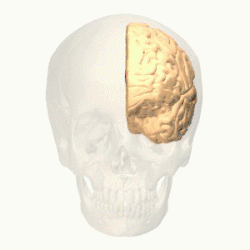

Figure 4. Prefrontal cortex of the left cerebral hemisphere.

The prefrontal cortex (PFC) is responsible for complex cognitive behaviour, decision making and consciousness (Burton, Westen, Kowalski, & Westen, 2015). While there is still much debate as to what specific role the different areas of the PFC play in anxiety related disorders, a review conducted by Spalding in 2018, investigated the role that the medial prefrontal cortex (mPFC) has in relation to fear generalisation - conditioned fear generalising to related stimuli, (Spalding, 2018). The study found that in human subjects, the ventral mPFC plays an important role in inhibiting the fear generalisation, while dorsal mPFC is seen to activate fear generalisation. Studies indicate that "higher levels of anxiety have been associated with increased activity in the dorsal mPFC (Straube et al., 2009), but further research needs to be done to investigate this.